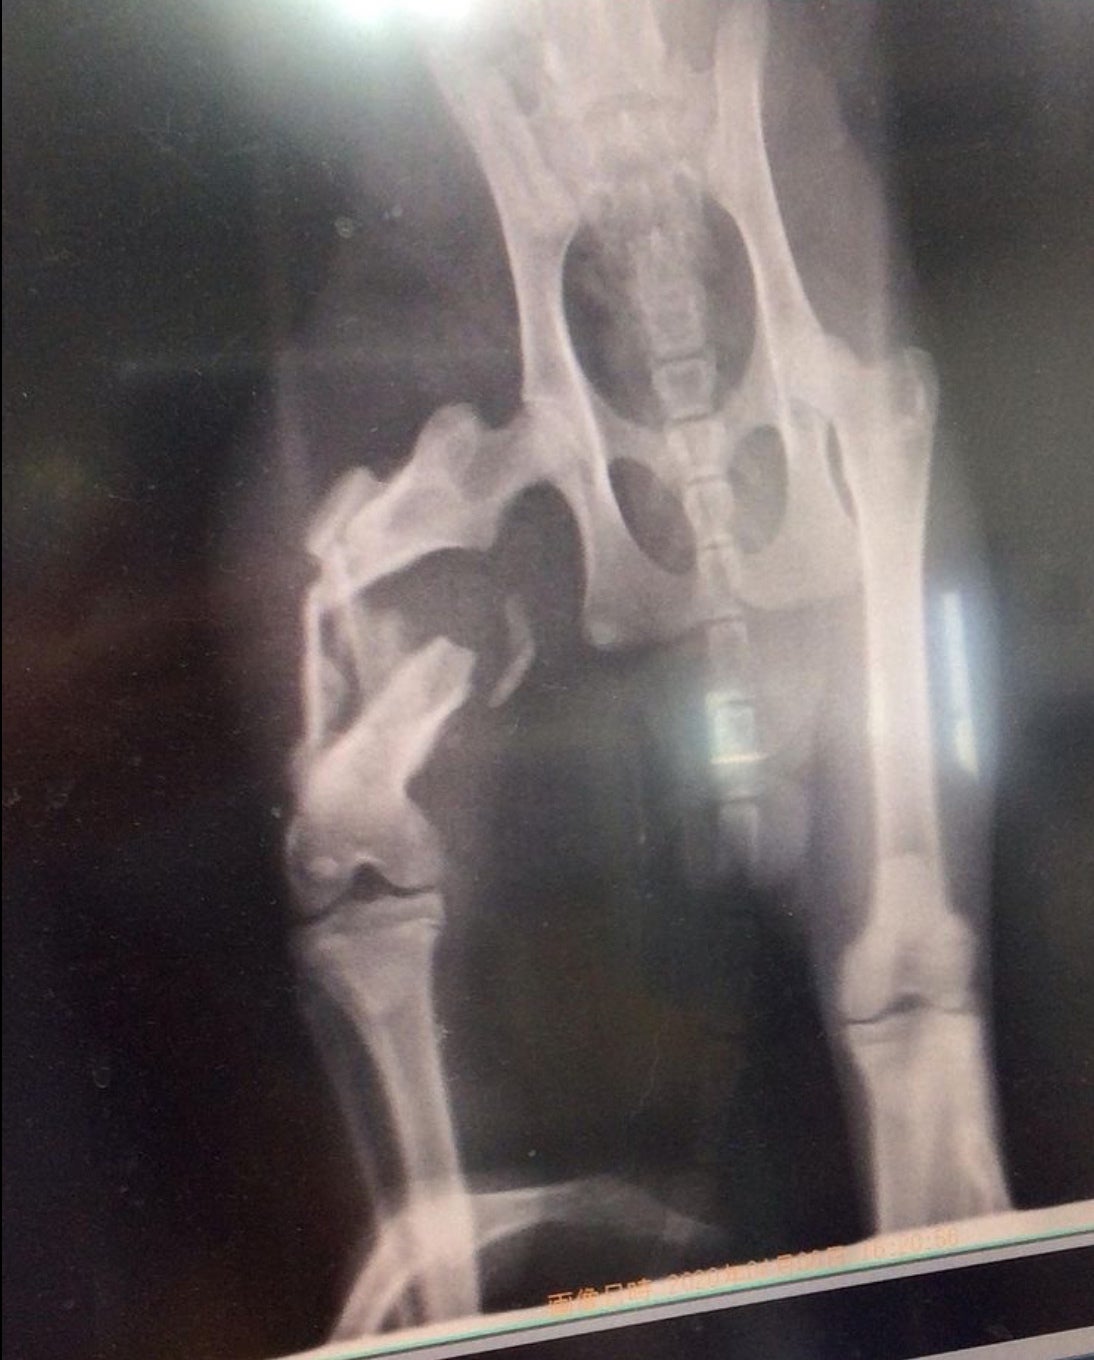

福岡県で足を引きずっている猫を発見し、その辺りの方に聞いたところ、

偶然にもそこでご飯をもらっていました。

その人が言うには、野良猫でご飯をあげていたが、車に轢かれ2週間ほど姿を消していたので、

死んだかなと思っていたそうです。そしたら、最近になってふらっと姿を見せたそうです。

人間が事故にあったら皆んな助けてくれるのに、猫の場合はほったらかしですか?

一人で2週間もの間 痛みに耐えていたんだね…

こんな辛い思いをした子を、放ったらかしにして帰ることが出来ず、保護させてくださいとお願いしました。

今では、本当に骨折してたの??と思うくらい走り回っています。